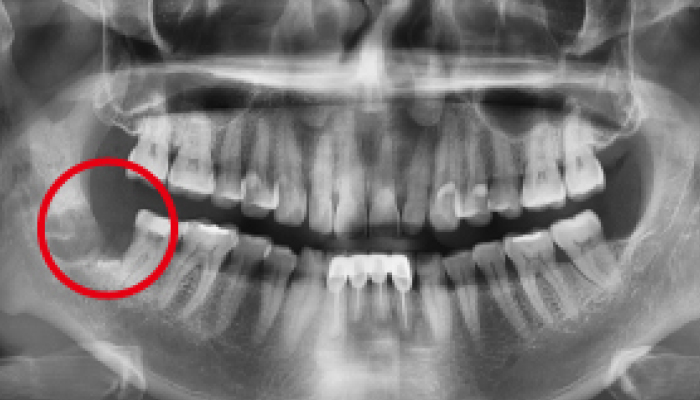

• 치료전

치료후